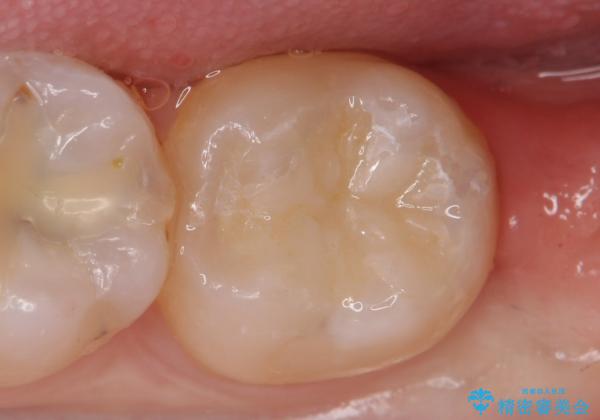

- 古い銀歯を白くしたいといらっしゃった方の症例です。

銀歯及び虫歯を除去後、セラミックインレーにて修復を行いました。

当院のセラミックインレーはemaxという強度と審美性に優れた材料を使用しています。

またプレス方式でインレーを製作しているため、削り出しで製作するCADCAMより優れた適合性も持ち合わせており、虫歯が再発しにくい修復物です。